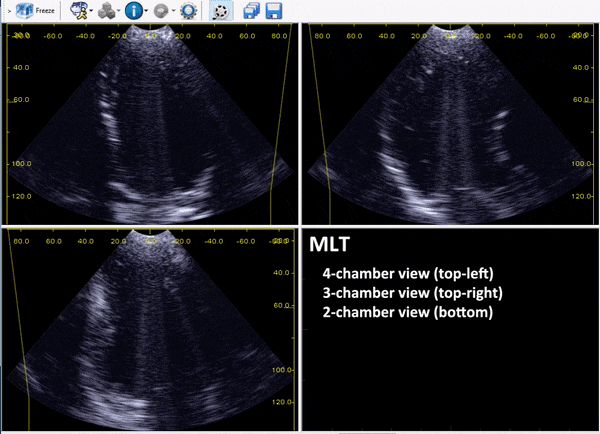

Real-time tri-plane echocardioraphy at high temporal resolution: in-vivo test.